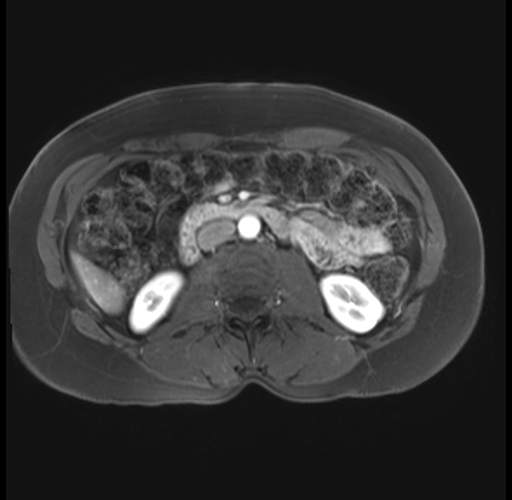

Imaging Analysis

Look through the patient's CT scan to identify any areas of concern for the necessary procedure.

Based on your CT findings, which issue(s) are present and would give reason for "planned slowing down moment(s)" in this case?